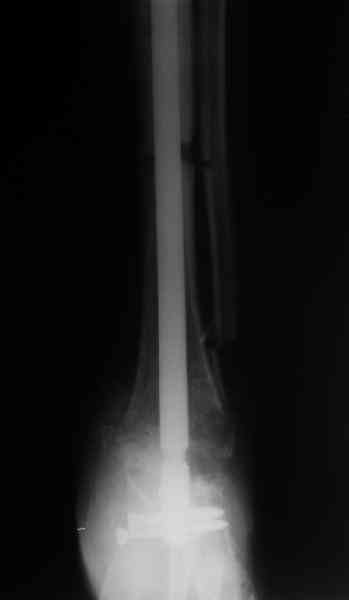

Приветствую, Павел и коллеги, ПИ> удлинения большеберцовой кости для компенсации укорочения поврежденной конечности. ПИ> В итоге: мы планируем выполнить пациенту большеберцово-пяточный ПИ> артродез в аппарате Илизарова с одновременной остеотомией берцовых В продолжение обсуждения, которое было 3 недели назад. Аналогичня операция одному нашему пациенту была сделана в конце февраля 2006. Дистракцию закончили 15 марта. На недавнем снимке нижний регенерат еще довольно хлипкий (снимок 1),

и мы не смогли обещать, что аппарат можно будет совсем скоро снять. Пациент выразил горячее желание расстаться с наружным фиксатором, даже если нужна еще одна операция. На этой неделе выполнили закрытое штифтование (впервые именно в такой ситуации) и сняли аппарат.

Стержень 12 мм, винт диаметром 6 мм, костная трубка вокруг хорошая. Перелом такого винта пока не наблюдали ни разу на нескольких сотнях

пациентов.